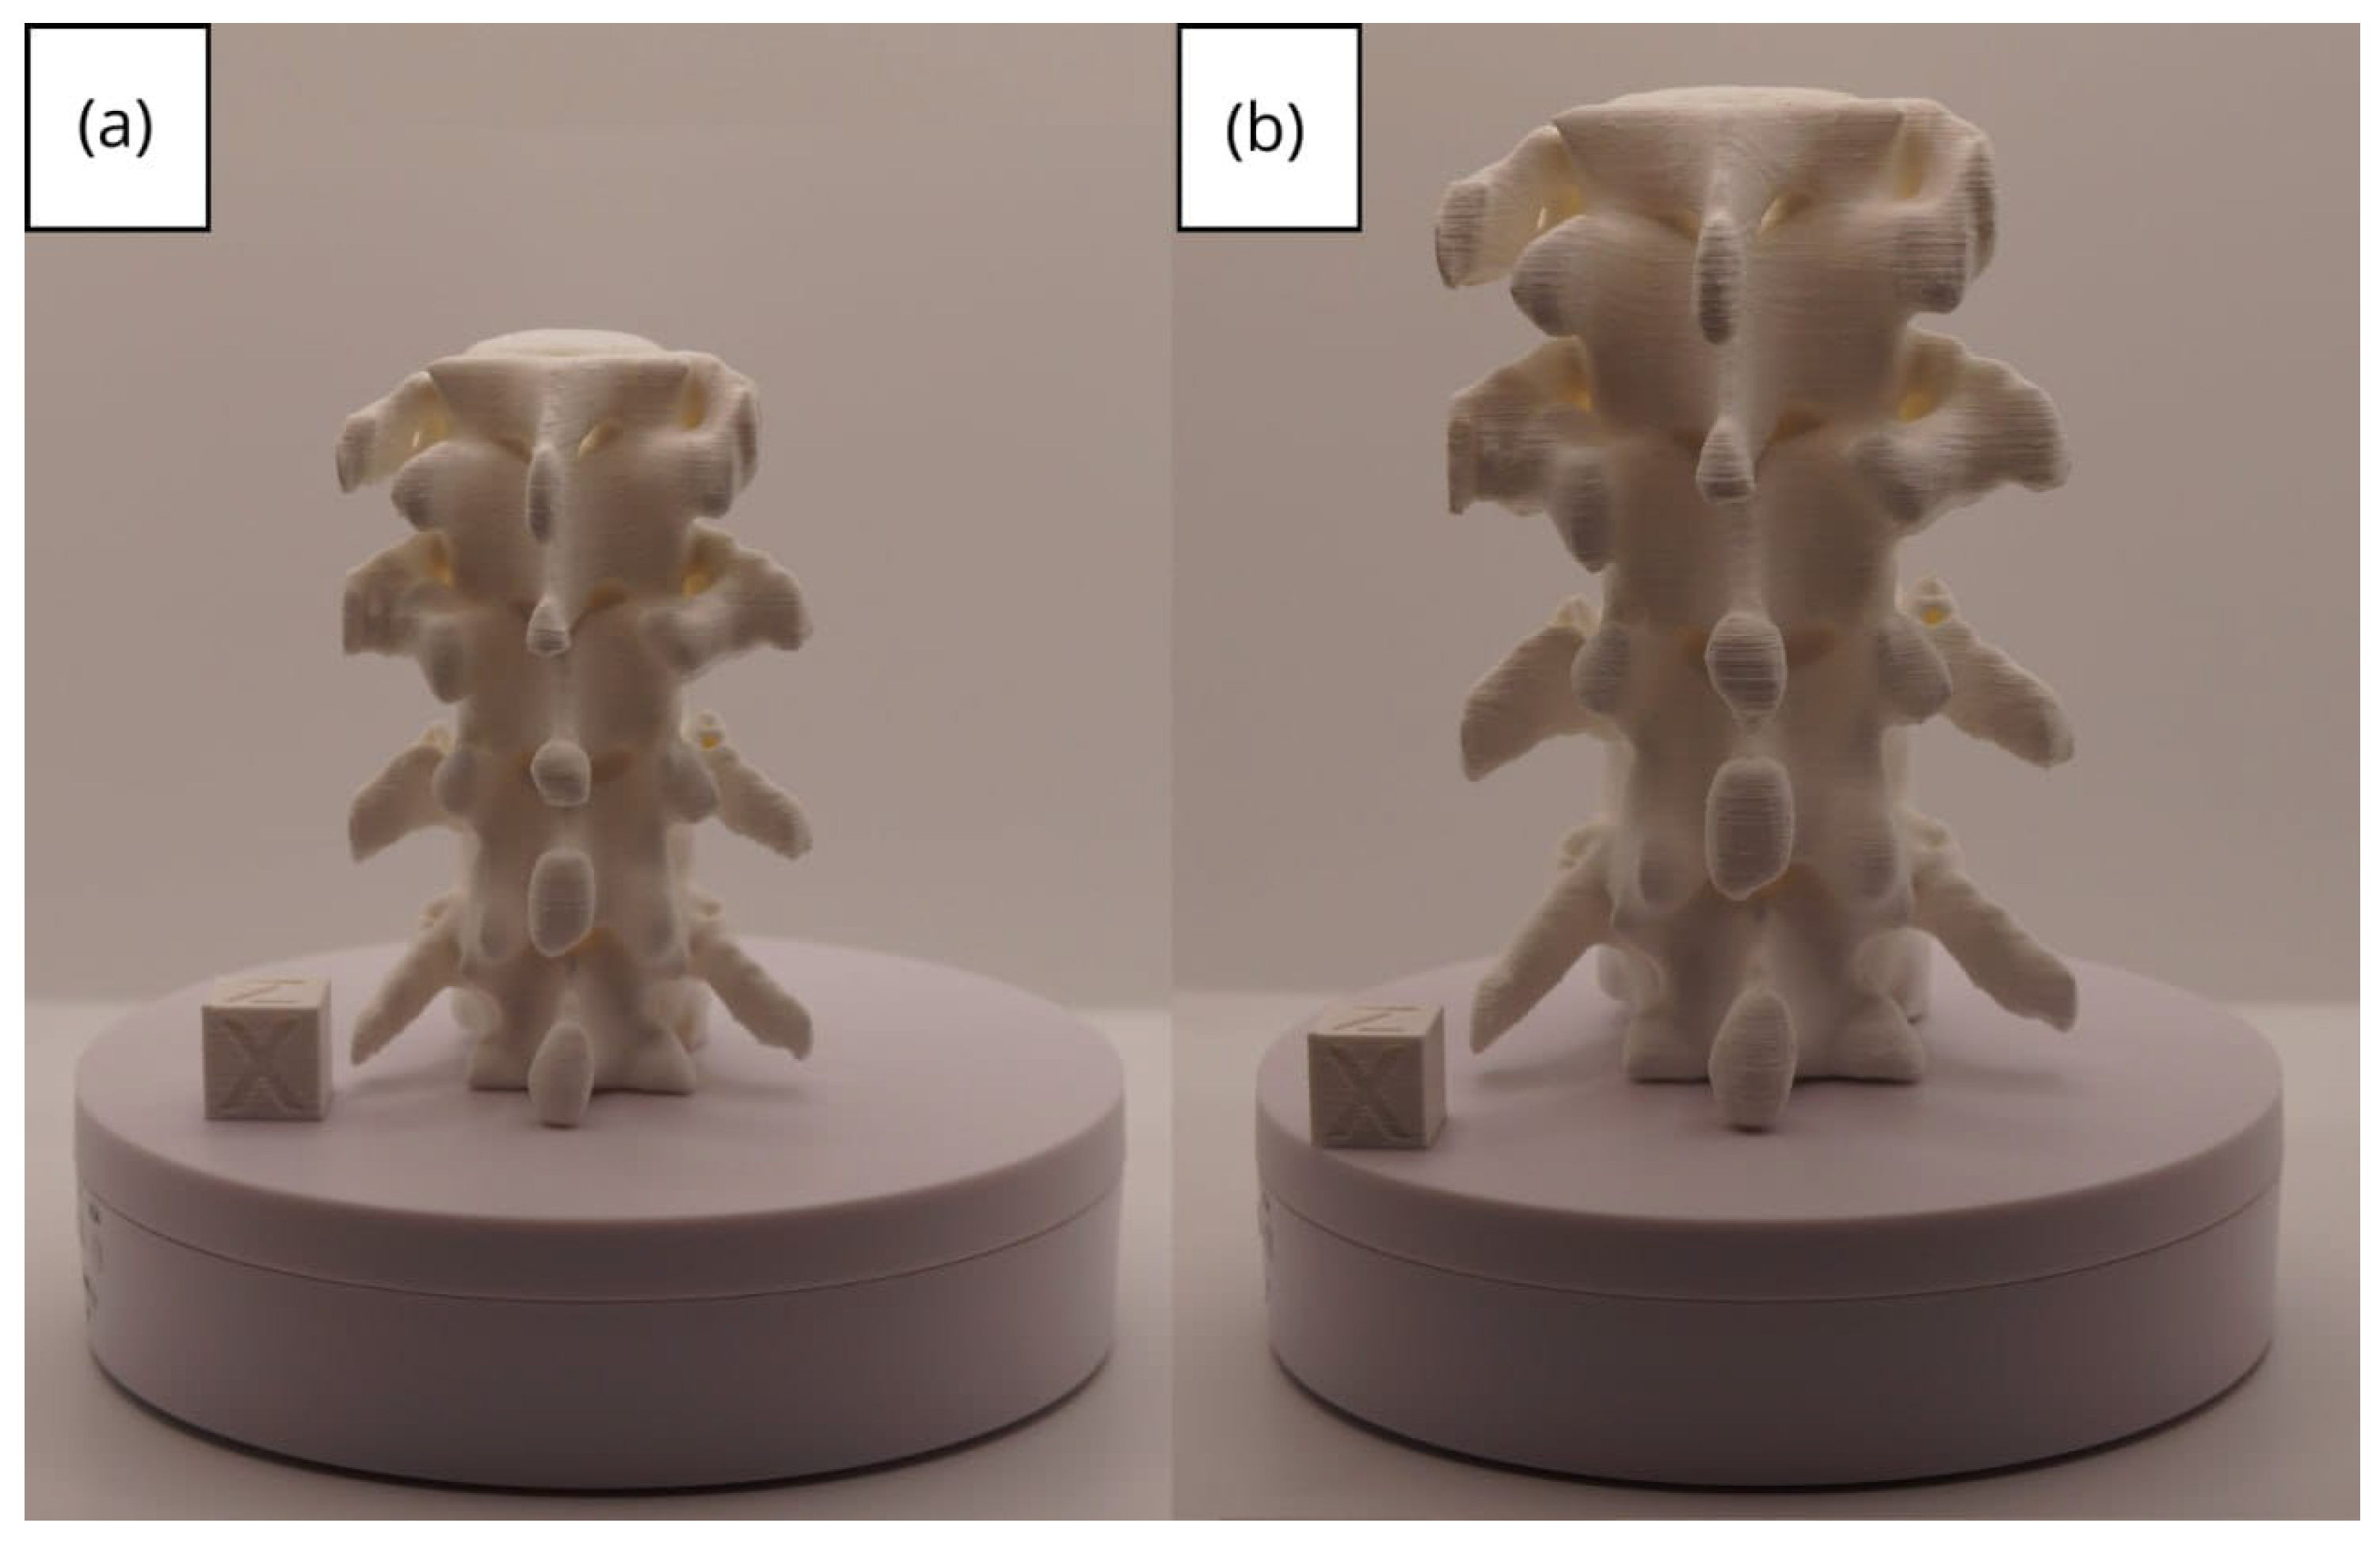

3.3. Human Brain Tumour

3.3.1. DICOM-to-STL Files

3.3.2. STL-to-GCODE Files

3.3.3. Final Printing

| Brain Tumour | [90, 220] | None | 0.8 | 0.20 | 25 |

| Brain tumour models | m; m | Artillery Sidewinder X2 |

| m; m | Creality Ender 3 |